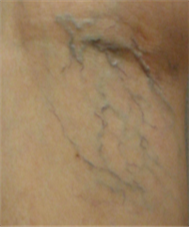

혈관은 아래의 사진들처럼,

아주 얇고 가는 실핏줄부터 지렁이 굵기의 튀어나온 혈관까지

다양한 모양으로 보일 수 있습니다.